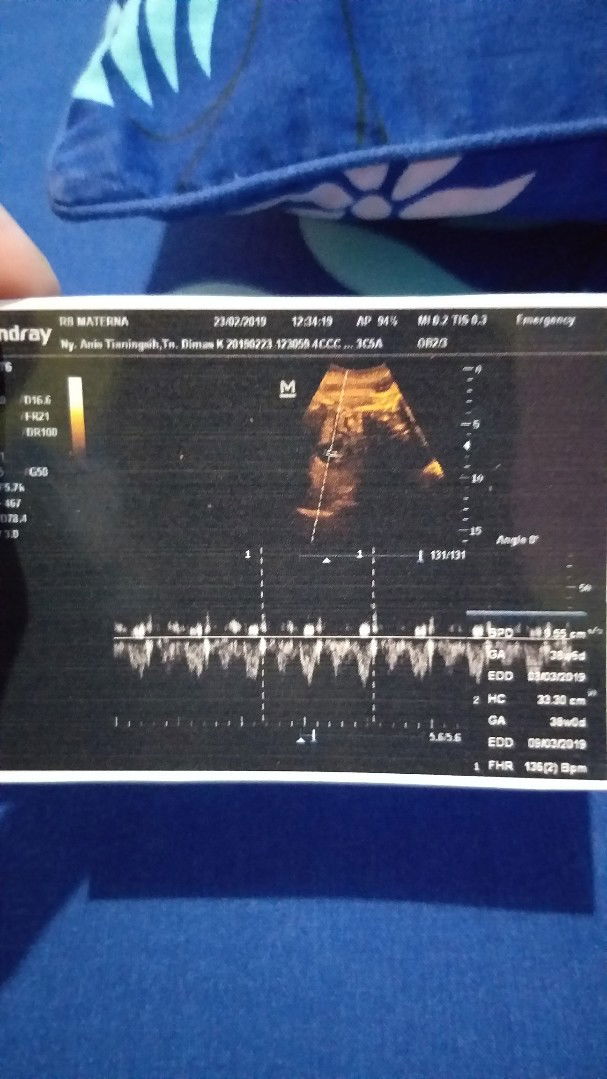

Teringat tanggal 12 maret 2019 dimana suami sedang cuti dan aku minta temenin check-up ke rumah sakit. Dikarenakan sudah mendekati HPL tapi belum ada tanda-tanda untuk lahiran. Rencananya setelah check-up mau pergi belanja kebutuhan si baby yang masih kurang. Pas sampainya dirumah sakit dicek dan diUSG jjrreeenggg.... si dokter bilang ini ibu kelebihan air ketuban entah apa nama kedokterannya. Setelah dijelasin besoknya harus SC dan harus dirawat mulai hari itu sedih tapi bahagia bisa ketemu si baby nanti. Yang tadinya punya rencana belanja, ngajakin suami makan pizza semuanya hilang kepanikan degdegan semua campur aduk karena lahir dadakan dan belum ada persiapan sambil nunggu suami mengurus persyaratannya saya cuma diam dikamar sambil tarik nafas harus tenang. Setelah proses suntik sana sini sakit sana sini tibalah besoknya ditanggal 13 maret 2019 lahir seorang malaikat kecil berjenis kelamin laki-laki bernama Arkana bayi sehat yang sholeh, laki-laki yang kuat "karena pas hamil saya bawa jalan terus sampai saya ajak main games tarik tambang ??" allhamdulillah suatu moment yang sangat bahagia dan sedih semuanya bercampur #senangnyajadiibu #CeritaHamilTAP